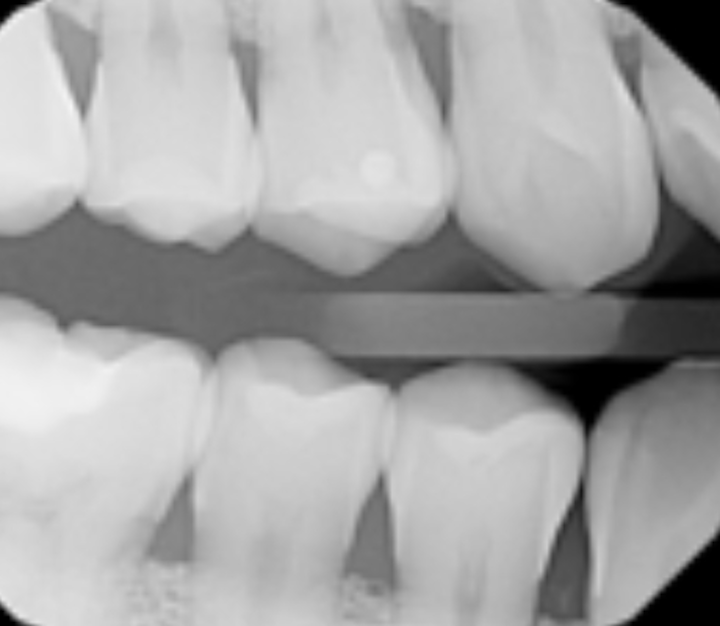

Dental XRay Full Mouth Series (FMX) Explained YouTube What Is Fmx Dental Code $50 + $30 + $15 = $95. This revised wording is carried forward to the cdt code’s comparable procedure codes (e.g., d0709 for image capture only). Learn what cdt dental fmx code is, how it helps detect hidden dental issues, monitor oral health progress, and guide orthodontic procedures. Another area of confusion is the practice of some third party payers. What Is Fmx Dental Code.